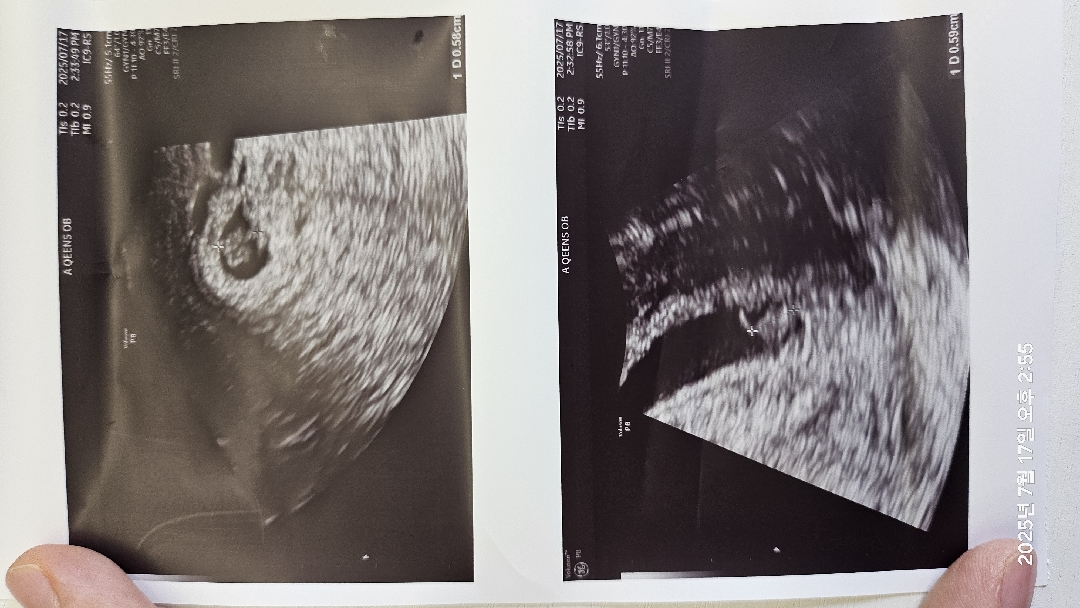

어제까지 미친듯 심하던 입덧이 오늘 잠잠해지면서 심리적으로 엄청난 불안이 와서 인근산부인과에서 초음파보고왔어요! 다태아 중 하나는 140대 하나는 110대 심장소리 차이가 많이나서 걱정이 너무 되서요 ㅠㅠ 아직 6주차라 다음주나 되야 정확한걸까요? 원래 심장소리 다음 주에 듣기로 되어있긴 하거든요;;

오늘 초음파 보려고 간건데... 심장소리 바로 들로주더라고요...ㅠㅠ 물어보자않고 바로 들려주시길래 안좋은지는 몰랐어요 ㅠㅠ 다음주 또 들어야할지 걱정되네요 ㅠㅠ